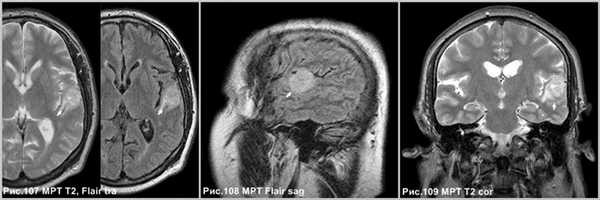

- Т1: солидный компонент изо- или гипоинтенсивный по отношению к серому веществу; кистозный компонент имеет низкую интенсивность сигнала, лептоменингеальное вовлечение в 70% случаев;

- Т1 с парамагнетиками: выраженное накопление контрастного вещества в солидном компоненте;

- Т2: солидный компонент изо- или гиперинтенсивный по отношению к серому веществу; кистозный компонент имеет высокую интенсивность сигнала; на Т2 FLAIR кистозные компартменты гиперинтенсивны по отношению к ЦСЖ из-за высокого содержания белков; небольшой вазогенный отек;